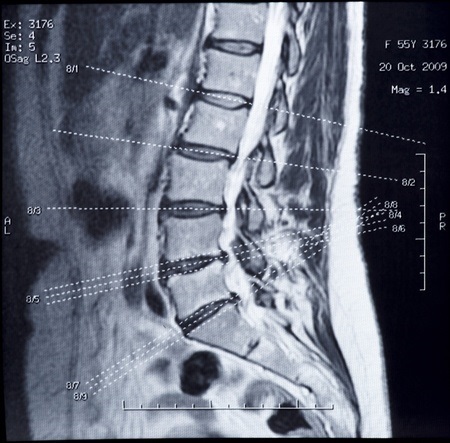

【奈美恵さん(33)の実例】レントゲン、MRIの検査結果により「あなたは椎間板ヘルニアです」と診断されました。飛びだした椎間板がきれいに映っています。

「この部分が神経を圧迫して痛みを作っています」と先生は言うのです…。

一般的常識として、ヘルニアと診断されたから痛いと考えてしまいますが、実はヘルニアでも痛みのない人がたくさんいます。痛みのない健康な方でも、「椎間板が飛びだしている人」はたくさんいると言うことです。

つまり、このヘルニアが痛みの根本原因ではないと言ううことです。腰痛の原因は患部には無い場合がとても多いのです。常識的診断と治療とは何なのか?!と考えさせられることがよくあります。